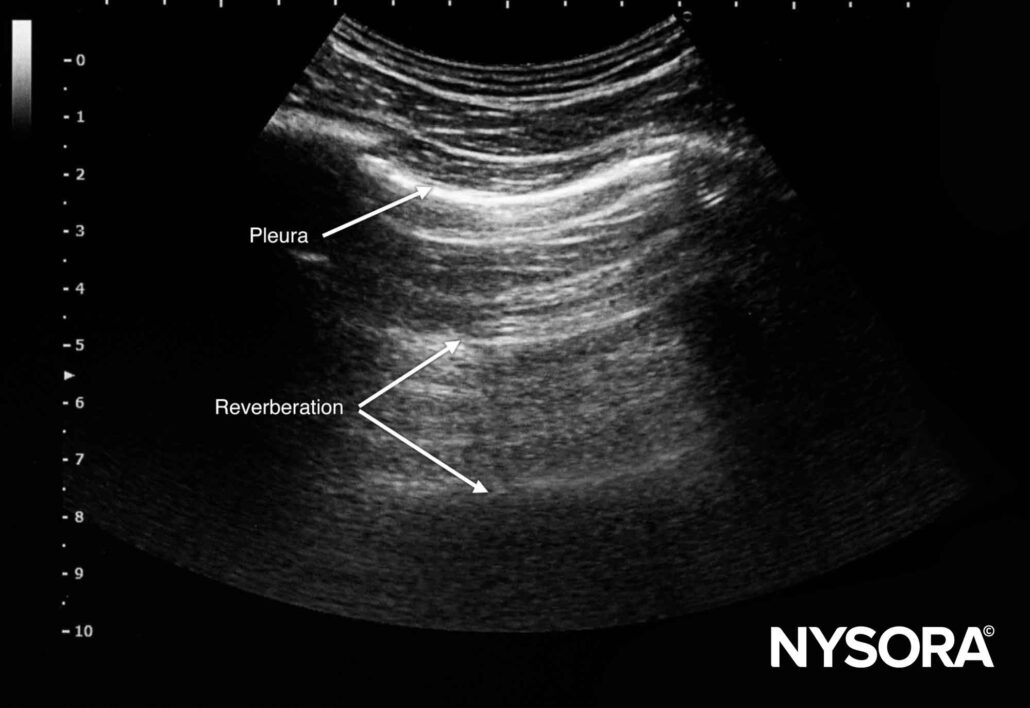

From www.nysora.com

Ultrasound image artifacts explained NYSORA NYSORA What Does Artifact Mean On Ultrasound artifact on an imaging test is something that is seen on an image as abnormal but does not represent a real. an artifact is something that you see on the ultrasound image which is either not really there, is in another place in reality, or looks different than it. ultrasound artifacts are commonly encountered and familiarity is. What Does Artifact Mean On Ultrasound.